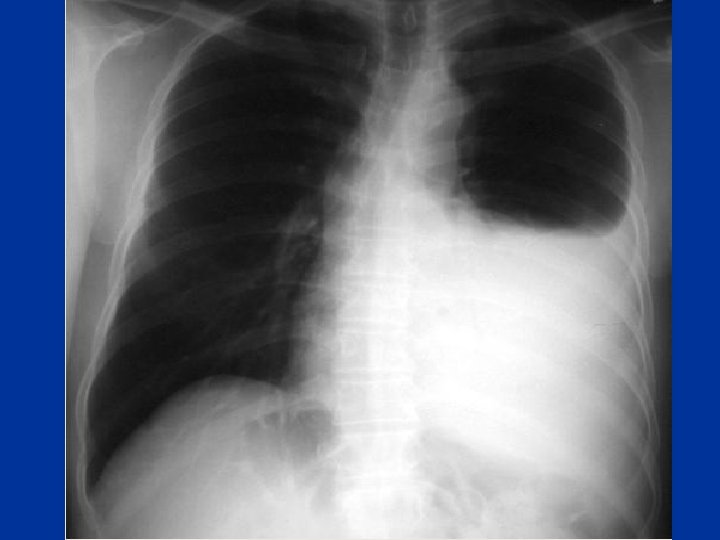

Pneumothorax • tall, thin, young patient. H/O pleural aspiration or biopsy • Symptoms: wheezes • one hemithorax • Hyperinflated • Hyperresonance • ↓ breath sounds • Trachea + mediastinal shift • CXR esp • exp. film

Pneumothorax • Major Types: • Spontaneous: Primary peak 20 -30 yrs, 4: 1 male : female • Tall thin , cigarette smokers, positive family history Secondary: Parenchymal lung disease e. g sarcoidosis, IPF, Emphysema, Necrotising pneumonia incl. Tb, PCP, • Iatrogenic: Pleural tap, transbronchial lung biopsy, positive pressure ventilation. • Traumatic: Rib fracture, bronchial rupture, esophageal rupture

Pneumothorax Mechanism • rupture of subpleural bleb or parenchymal process eroding visceral pleura this may also cause partial bronchial obstruction(check -valve mechanism) & hyperinflation

Complications • Tension Pneumothorax When significant positive pressure in the pleural space results in severe compression of ipsilateral lung, contralateral shift of the mediastinum • Results from one way valve mechanism • how to diagnose ? • What to do?

Pneumothorax management • Observation: in small pneumothorax(<15%) primary , spontaneuos or iatrogenic not ventilated • Oxygen; Increase the pressure gradient between pleural space&capillaries by decreasing partial pressure of nitrogen • chest tube • thoracotomy